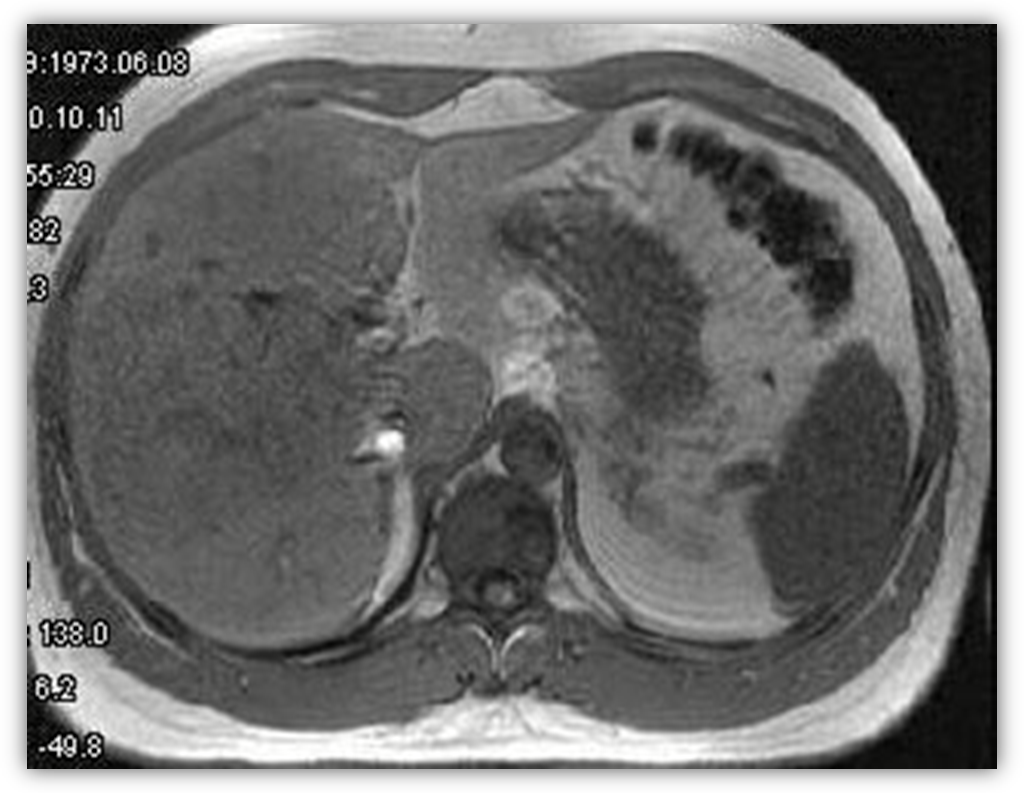

4. МРТ печінки

При проведенні МРТ печінки виявлені зменшена в розмірах печінка з вузлуватими контурами, варикозно-розширені вени.